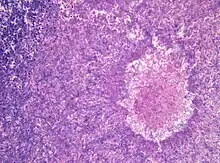

| Aspergillomas complicating tuberculosis: multiple aspergillomas within large cavitary lesions of tuberculous origin. | |

Although most fungi—and especially Aspergillus—fail to grow in healthy human tissue, significant growth may occur in people whose adaptive immune system is compromised, such as those with chronic granulomatous disease, who are undergoing chemotherapy, or who have recently undergone a bone marrow transplantation. Within the lungs of such individuals, the fungal hyphae spread out as a spherical growth. With the restoration of normal defense mechanisms, neutrophils and lymphocytes are attracted to the edge of the spherical fungal growth where they lyse, releasing tissue-digesting enzymes as a normal function. A sphere of the infected lung is thus cleaved from the adjacent lung. This sphere flops around in the resulting cavity and is recognized on x-ray as a fungus ball. This process is beneficial as a potentially serious invasive fungal infection is converted into surface colonization. Although the fungus is inactivated in the process, surgeons may choose to operate to reduce the possibility of bleeding. Microscopic examination of surgically removed recently formed fungus balls clearly shows a sphere of dead lung containing fungal hyphae. Microscopic examination of older lesions reveals mummified tissue which may reveal faint residual lung or hyphal structures.[5]